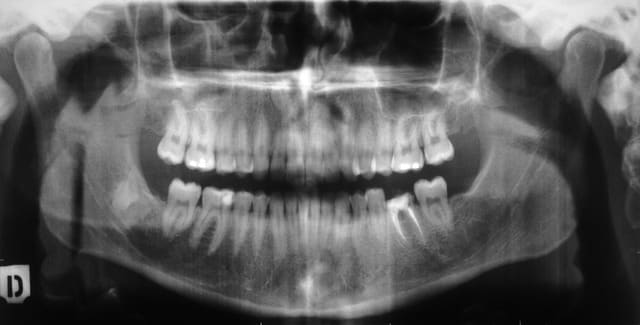

Patiente de 22 ans, santé et ATCD RAS.

Bio de 36 réalisée il y a 6 ans. "Reconstitution" coronaire par IRM.

Le cone beam objective la lésion inter-radiculaire, voie d'entrée linguale.

Je ne sais pas encore si le plancher est costaud ou non. Mais vu la lésion j'ai quelques inquiétudes.

ps : sur la pano je ne sais pas à quoi correspond l'image au niveau de l'ex-48. Ca me parait un peu loin pour être une racine de l'ex-48 elle-même.

@Cartman : J'ai fait faire le cone beam pour savoir où je mettais les pieds au niveau paro/endo. L'atteinte de la furcation est quand-même bien avancée, pas décelable au sondage. En général je n'en fais pas faire pour ça.